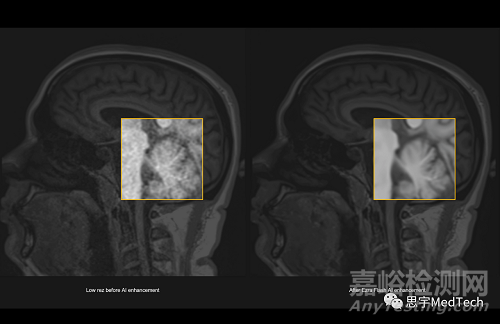

據(jù)悉,Ezra使用其專有的縱向MRI數(shù)據(jù)集來(lái)訓(xùn)練AI,該數(shù)據(jù)集包括數(shù)十萬(wàn)張患者和健康受試者的MRI圖像。

Ezra還訓(xùn)練AI評(píng)估哪些元素對(duì)于生成完整和準(zhǔn)確的圖像是必不可少的。這使得Ezra能夠在高速M(fèi)RI掃描中提高圖像質(zhì)量,這些掃描已經(jīng)達(dá)到了當(dāng)前護(hù)理標(biāo)準(zhǔn)的極限 。

▲(圖左為未使用AI技術(shù)形成的MRI圖像,圖右為Ezra Flash AI增強(qiáng)后圖像)